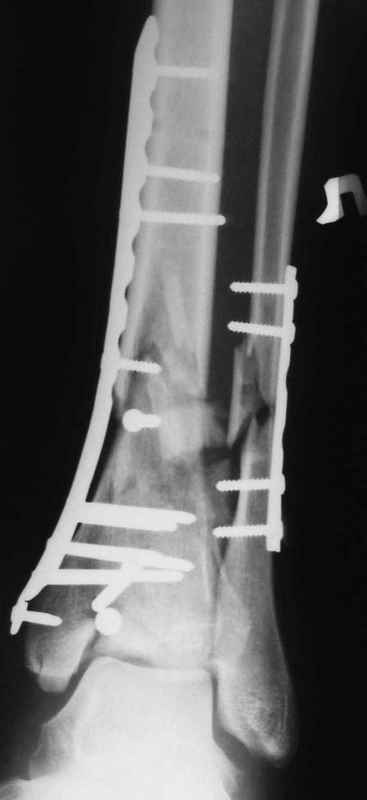

Классическая последовательность открытой редукции состоит из следующих этапов: 1-Восстановление длины и фиксация перелома малоберцовой кости

2 - Реконструкция суставной поверхности большеберцовой кости. 3 - Заполнение

метаэпифизарного дефекта свободным костным трансплантатом. 4 - поддерживающая фиксация с помощью накостных пластин.

На сегодняшний день, стандартом лечения переломов pilon являются протоколы, включающие наложение наружных фиксаторов на 1-3 недели для поддержания длины и восстановления мягких тканей с последующей закрытой или открытой репозицией перелома большеберцовой кости и фиксацией наружным аппаратом в комбинации с минимальной внутренней фиксацией или без неё, ± фиксация малоберцовой кости с помощью платы и шурупов. Голеностопный сустав фиксируется в аппарате 6-12 недель, после чего начинается его разработка, общий срок фиксации в аппарате 12-16 недель, а для переломов проникающих до диафиза – 6 месяцев.